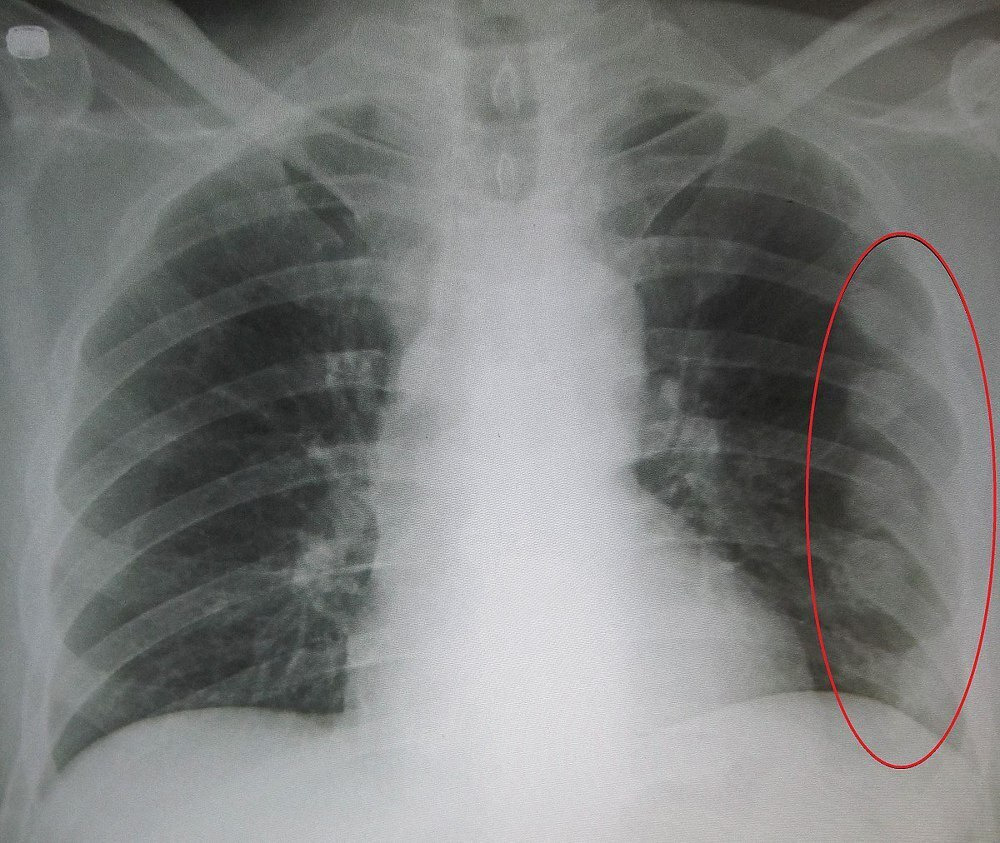

갈비뼈 손상은 호흡 시마다 갈비뼈가 움직이기 때문에 통증을 유발하여 호흡을 얕게 만듭니다. 이로 인해 산소 부족을 경험할 수도 있으며, 심각한 경우 폐에 손상이 생길 가능성도 있습니다. 심각한 호흡 곤란이 발생하면 반드시 응급실을 방문하여 폐 손상 여부를 확인해야 합니다.

호흡 곤란은 종종 숨이 차거나 심장 박동이 빨라지는 증상과 함께 나타날 수 있습니다. 이 경우 적절한 산소 공급이 필수적이며, 지속적인 증상 관찰과 전문적인 치료가 필요합니다.